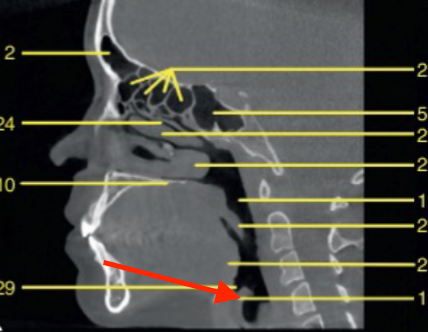

sagittal

what plane is this

C2 odontoid process

what is 43

coronoid process

what is 52

mandibular condyle

identify structure

glenoid fossa

identify the structure

articular eminence

hyoid

sella turcica